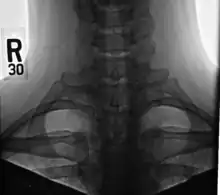

A cervical rib in humans is an extra rib which arises from the seventh cervical vertebra. Their presence is a congenital abnormality located above the normal first rib. A cervical rib is estimated to occur in 0.2%[2] to 0.5%[3] (1 in 200 to 500) of the population.[4] People may have a cervical rib on the right, left or both sides.[5][6]

Most cases of cervical ribs are not clinically relevant and do not have symptoms;[7][8] cervical ribs are generally discovered incidentally, most often during x-rays and CT scans.[3][4][6] However, they vary widely in size and shape,[3] and in rare cases, they may cause problems such as contributing to thoracic outlet syndrome,[7] because of pressure on the nerves that may be caused by the presence of the rib.[7][9]

On imaging, cervical ribs can be distinguished because their transverse processes are directed inferolaterally, whereas those of the adjacent thoracic spine are directed anterolaterally.[11]